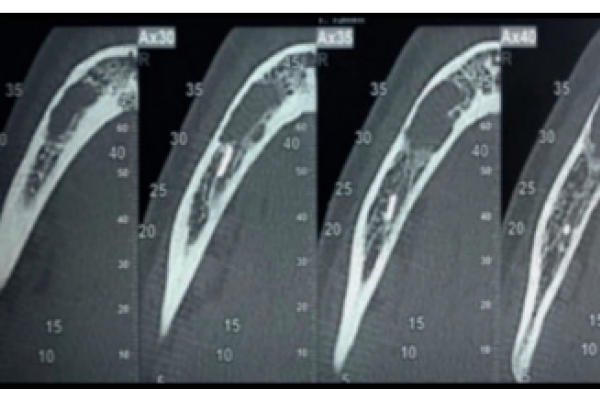

Injerto pediculado palatino en regeneración ósea guiada